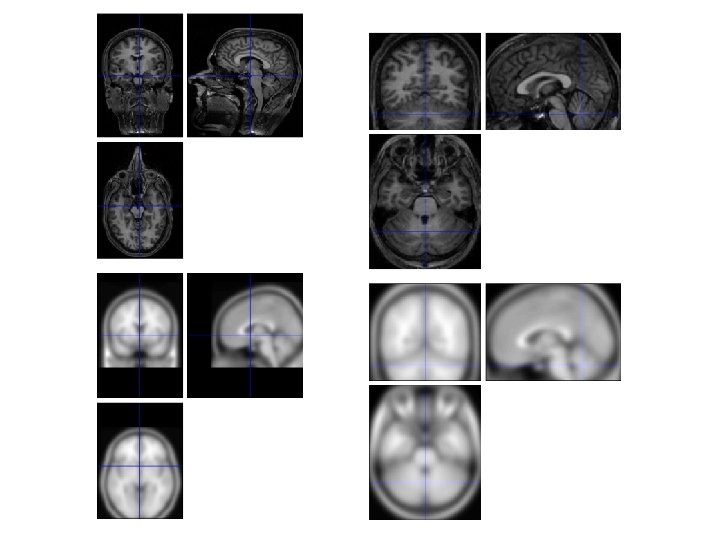

Co-registration • Refers to any method for realigning images – Realignment for motion correction (last week) – Aligning or overlaying images from different modalities T 2* EPI image (low resolution) T 1 structural MR image (high resolution)

What is Normalisation? Warps images from different participants onto a template brain Matthew Brett

SPM: Spatial Normalisation • SPM uses a voxel-intensity-based approach to normalisation. • adopts a two-stage procedure : • Step 1: Linear transformation (12 -parameter affine). This step accounts for the major differences in head shape and position, but there will be remaining smaller-scale differences. • Step 2: Non-linear transformation (warping). The non-linear step is designed to take care of the smaller-scale differences in brain anatomy. Alternatives – anatomy based approaches e. g. Free. Surfer

Step 1: Affine Transformation • Determines the • optimum 12 -parameter affine transformation to match the size and position of the images 12 parameters = 3 translations and 3 rotations (rigid-body) + 3 shears and 3 zooms Rotation Shear Translation Zoom

Step 2: Non-linear Registration • The model for defining nonlinear warps uses deformations consisting of a linear combination of low-frequency periodic basis functions.

Over-fitting and Regularisation Template image Non-linear registration using regularisation. Affine registration Non-linear registration without regularisation.